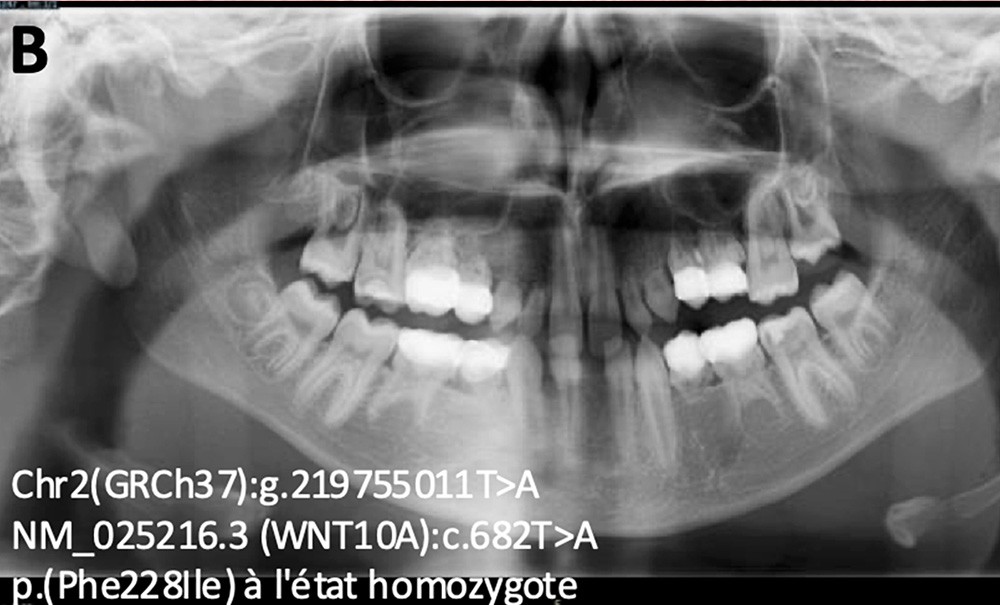

Ces modèles sont conçus pour être explicables (via la méthode SHAP ou Grad-CAM), garantissant transparence, éthique et confiance dans un usage clinique. Les résultats montrent déjà une capacité de prédiction de certains variants pathogènes pour les agénésies dentaires et les hypo/oligodonties (par exemple dans les gènes PAX9 ou WNT10A) à partir du patron de dents manquantes observé [5, 6] dans ces maladies rares (fig. 1).